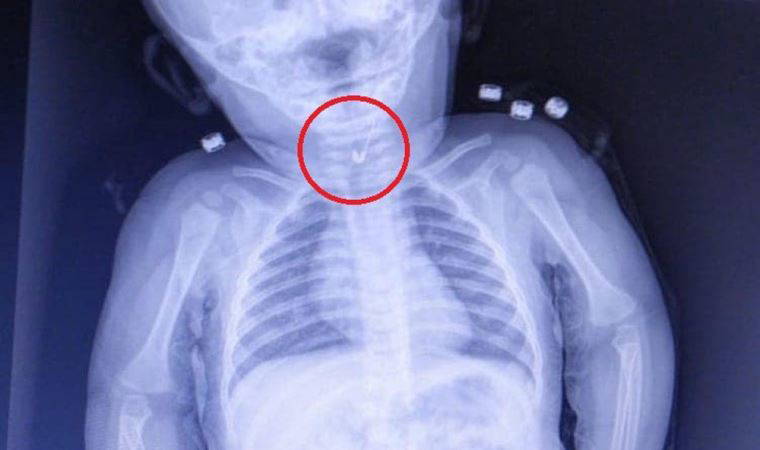

Ameliyat sonrası bir hafta boyunca röntgenlerle kontrol edilen mıknatısların çalışması, Deneen'in ailesini sevince boğdu.